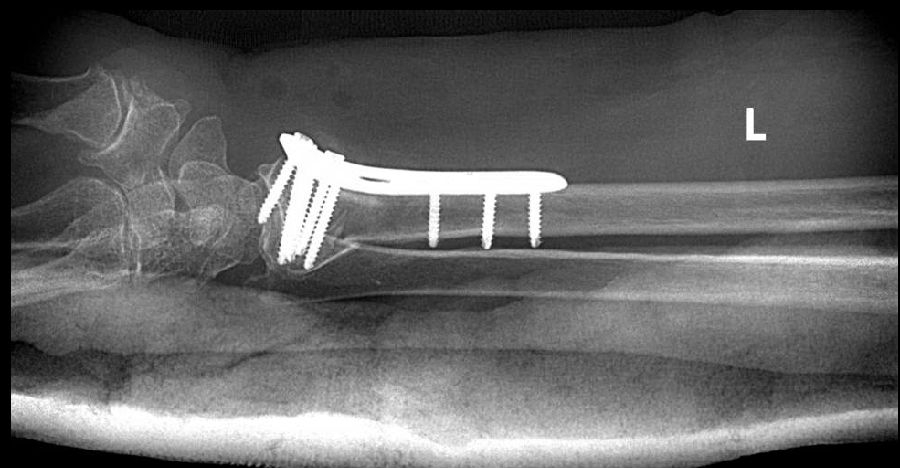

2、左桡骨远端骨折

2、左桡骨远端骨折切复内固定术